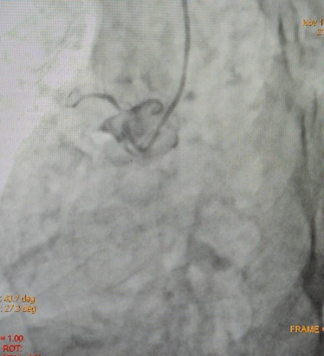

Coronary angiography showed single vessel coronary artery disease with long segment myocardial bridge in mid LAD, RCA-Totally occluded from its ostial part with retrograde filling by left system.

Figure 4: RCA-Totally occluded from its ostial part.

Figure 5: Failed PCI to RCA.